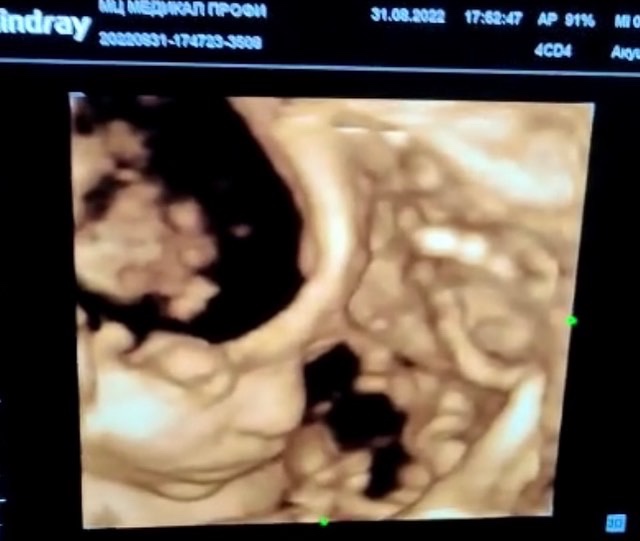

#4дузи это что-то!

Месяц ждала, и вот вчера мы съездили и сделали это!

Очень повезло с врачом. Очень внимательная, никуда не спешила. Крутила датчик минут 30 точно. Но сынок решил лежать уткнувшись лицом в плаценту, причем именно в месте прикрепления, что очень мешало его увидеть. Врач смотрела по-всякому, показывала нам каждый пальчик, все объясняла, рассказывала, и почти под конец, когда мы уже почти отчаялись, она чудом смогла уловить момент когда малой развернулся и буквально за секунду сд...